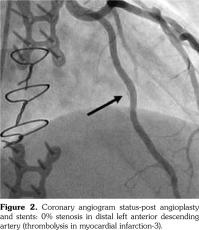

On admission, troponin was 0.05 ng/mL and electrocardiogram revealed sinus tachycardia with peaked T-waves in leads I, aVL, and V5-V6; and inverted T-waves in leads III and aVF. Echocardiogram demonstrated left ventricular hypertrophy with an ejection fraction of 55%. Selective coronary angiography (Figure 1) disclosed a 70% stenosis of the left internal mammary artery graft to the left anterior descending coronary artery and a 99% stenosis in the distal left anterior descending artery. Patient was treated with coronary angioplasty and two drug-eluting stents, reducing stenoses to 0% per final angiography (Figure 2).